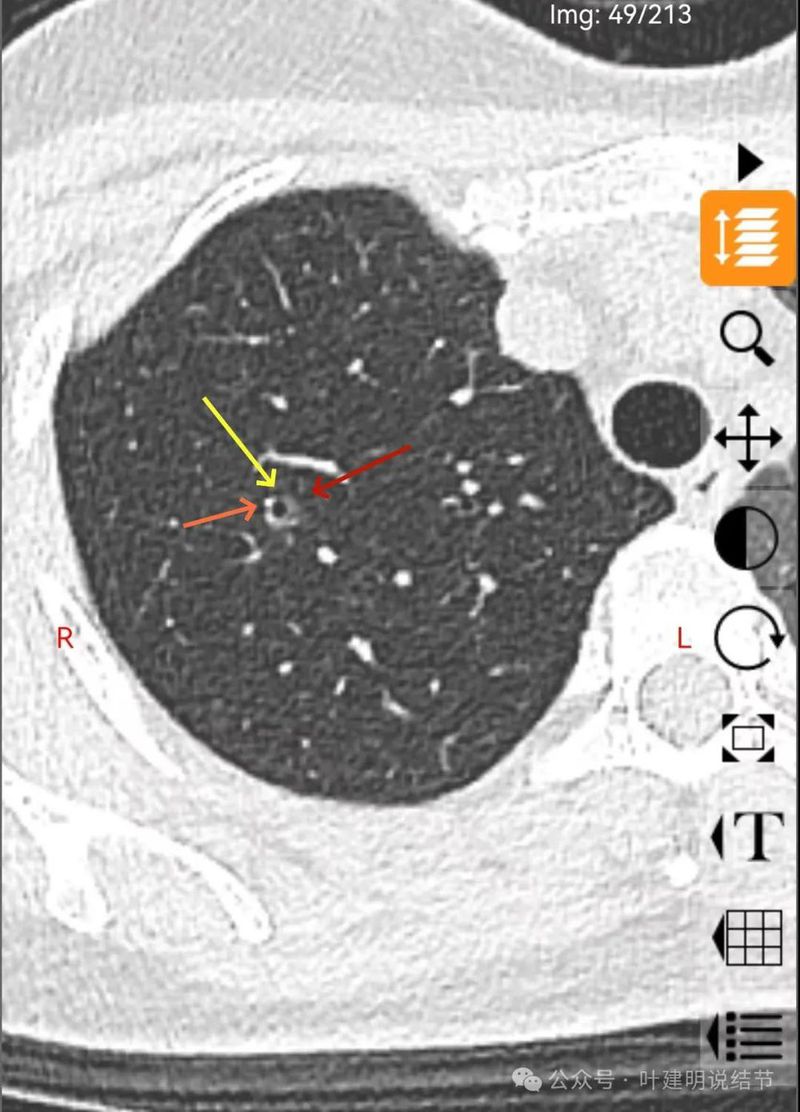

分叶状明显,支气管扩张明显,血管弯征可见,整体轮廓清。

灶内支气管扩张,附近血管有异常增粗,表面不平。

形态不规则、轮廓与边界清、多支血管进入穿行、支气管扩张,表面不平。